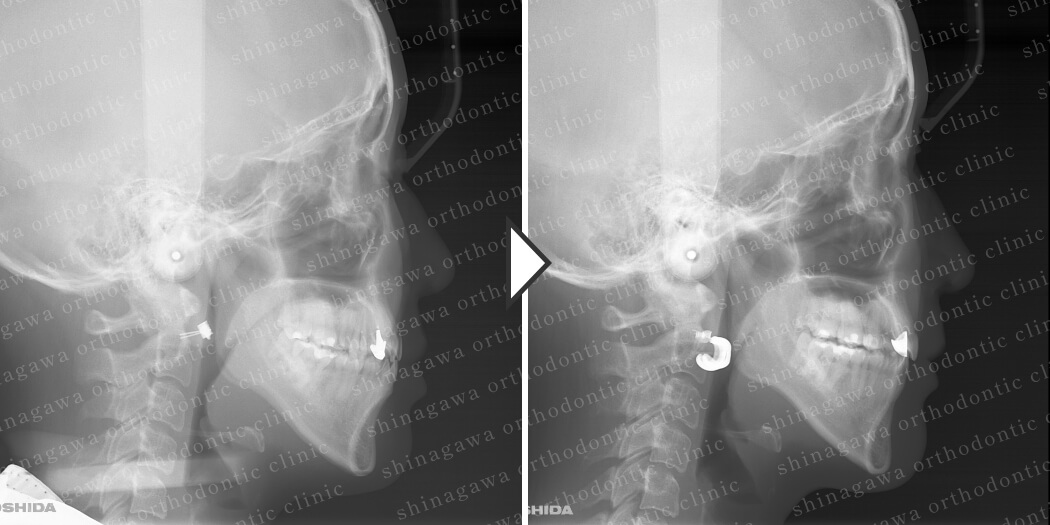

症例5

下顎前突、叢生

| 年齢 | 28 歳 |

|---|---|

| 性別 | 男性 |

| 住所 | 埼玉県浦和市 |

| 主訴 | ガタガタしている, 受け口 |

| 不正咬合の種類(診断) | 叢生, 下顎前突 |

| 装置 | リンガル |

| 抜歯/非抜歯 | UR4, UL4, LR4, LL4 |

| 期間 | 30M |

| 費用 | 1,430,000 円 |

| リスク・副作用 | 矯正治療による歯の移動に伴う痛み, 虫歯, 歯肉退縮, 歯根吸収 |